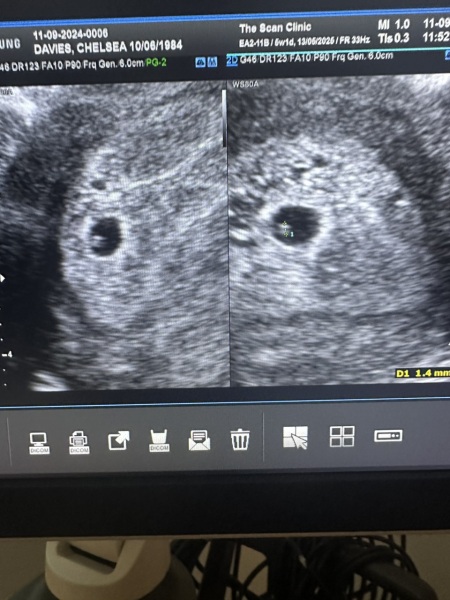

The doctor was lovely, he said I was 5weeks1 day pregnant and said he couldn't pick up a heartbeat as it's too early but confirmed I was pregnant and left feeling happy. I then got home and read the report and it says " no clear yolk sac or FT" I then went down a rabbit hole that I should see a yolk sac at 5 weeks and that I most likely not pregnant.

In the meantime, I'd edit the post because your name and details are on it. Here's a cropped version you can use instead.